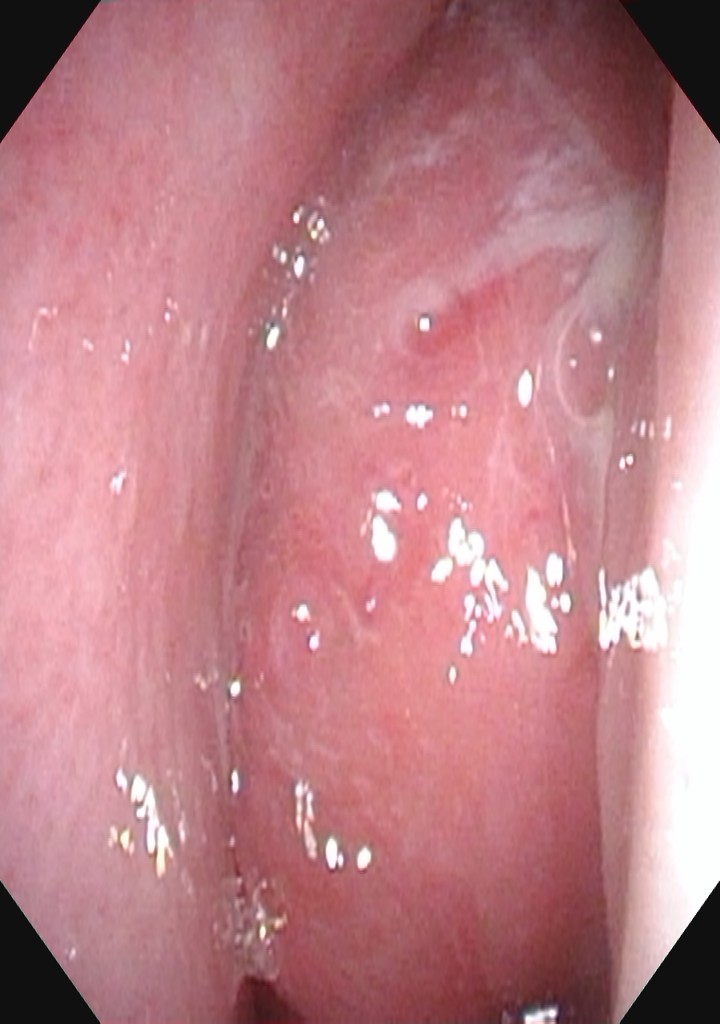

家住长沙雨花区的9岁6月男孩阔阔,在1月前出现鼻塞,流脓涕、口腔内有水泡,家长当时觉得就是个“小感冒”,未引起重视。后来他突然说右侧面部胀痛及头痛,家长才带他到当地社区医院就诊,血常规提示感染指标高,予抗生素抗感染治疗,但症状未见好转,而且头痛越来越厉害,于是家长带其来到湖南省儿童医院,耳鼻咽喉头颈外科医师为其行电子鼻咽喉镜检查发现其右侧鼻腔有一新生物。为了明确肿物来源及与周围组织的关系,予其行MR平扫+增强,结果示右侧鼻腔及筛窦区可见一大小约3.6x4.6x4.8cm类圆形混杂密度肿块影,边界较清晰,肿块部分凸入右侧上颌窦及眶锥内,右侧内直肌及视神经局部受压,鼻中隔局部受压向左侧移位,提示右侧鼻腔及筛窦区占位性病变:骨化性纤维瘤?手术是本病唯一根治的方法,为了保证手术安全及手术精准性,减少术中出血,耳鼻咽喉头颈外科进行了病例讨论,为患儿制定了个性化手术方案,目前阔阔已经顺利通过手术,鼻塞、头痛症状得到了明显改善。